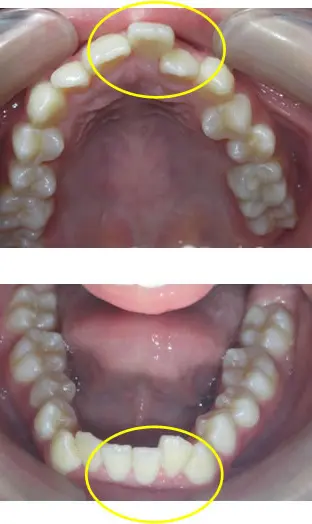

前歯の凸凹だけが問題なのでしょうか?

本来、この方が本来成長するはずであったところは上記のような上下顎のイメージになります!

顎が成長して(咀嚼や周囲の筋肉の調和などにより)歯が並ぶのに十分なスペースができさえすれば、乱れて生えてきた歯は自然に本来その歯が並ぶべき位置まで動いていってくれるという発想です